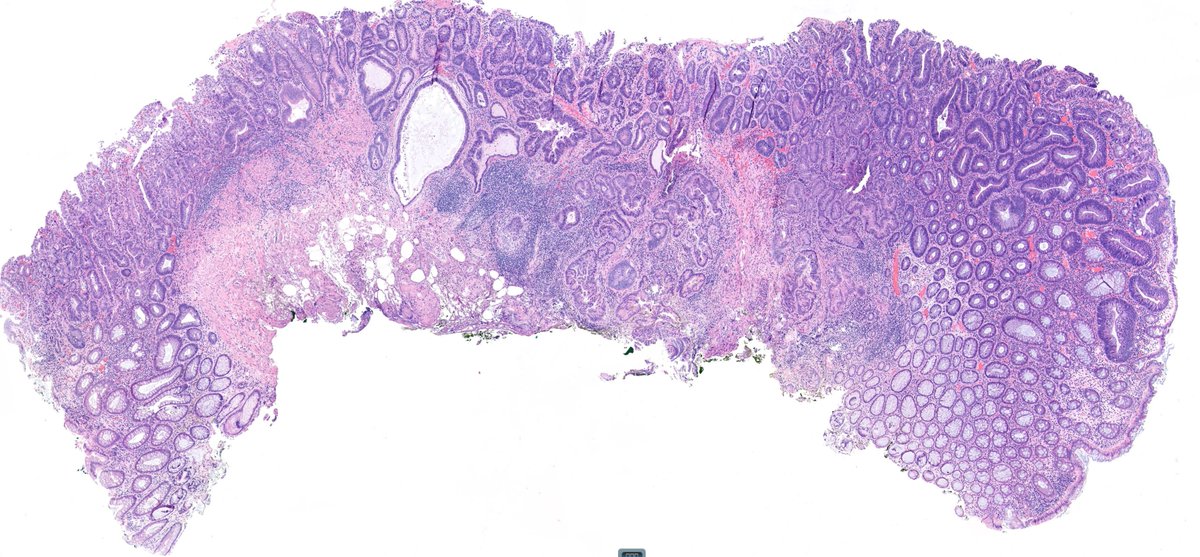

Rectal polyp. Pseudoinvasion or a pT1? A case of epithelial displacement vs pT1, before #GIpath short course at #USCAP23 What do you think?🤔

Misplaced adenoma with high-grade dysplasia? Invasive adenocarcinoma -pT1? Wouldn't you love to know what the GI pathology gurus would call this? Do come to our short course - featuring Deepa Patil and Reet Pai #USCAP23 #GIpath